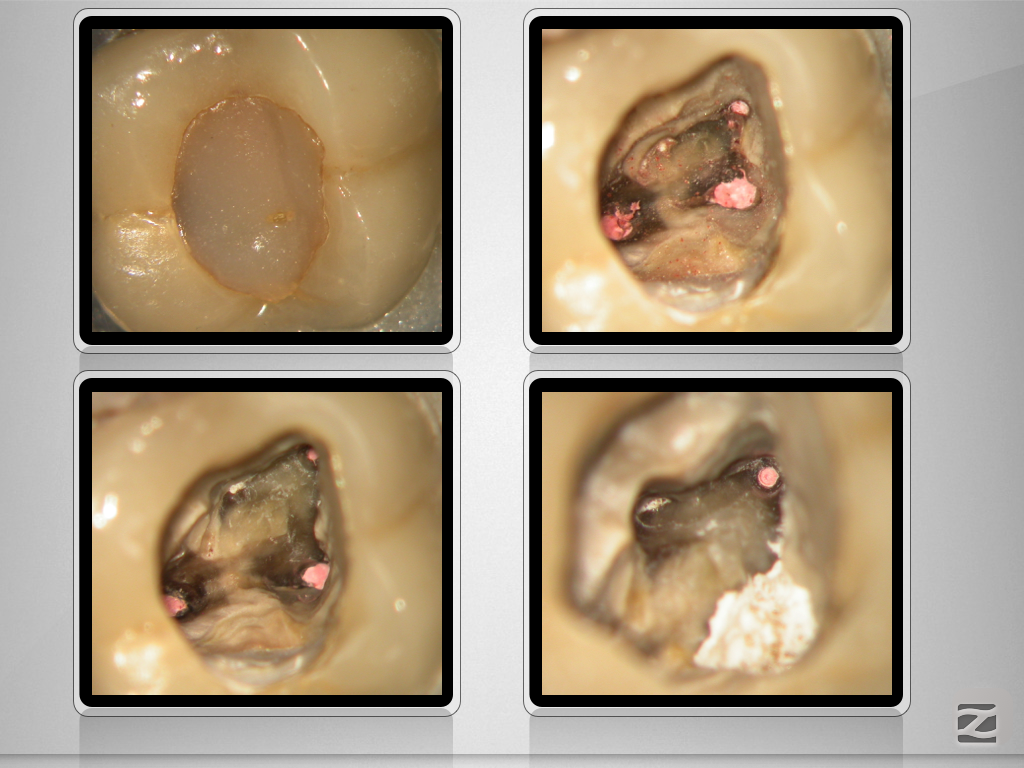

16D.005

Von allem etwas …